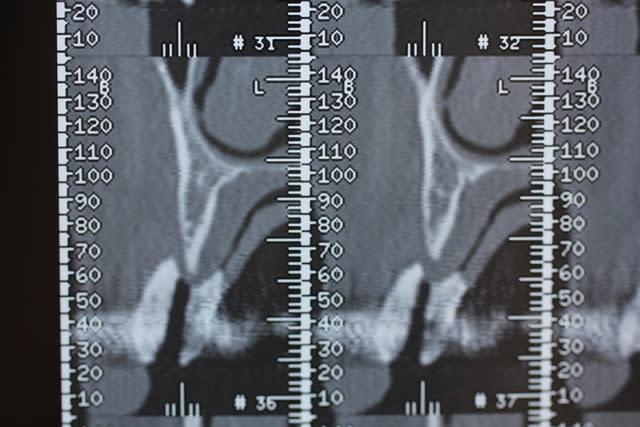

On est en 13 14 15, patiente d'une soixantaine d'années, sans antécédents médicaux ni dentaires. Un peu frileuse pour les grosses chirs mais elle était néanmoins partante pour les implants.

il semble y avoir une belle perte en hauteur aussi en distal de 12 sur la pano mais qu'on voit moins sur les coupes.

Pour moi c'est greffe onlay, mais j'aimerais bien voir exactement les coupes juste en distal de 12.

Ce sont les dernières coupes qui correspondent au site de la 13